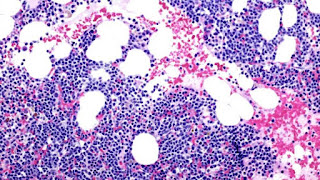

A bone marrow biopsy is usually performed to estimate the percentage of bone marrow occupied by plasma cells. This percentage is used in the diagnostic criteria for myeloma. Immunohistochemistry (staining particular cell types using antibodies against surface proteins) can detect plasma cells which express immunoglobulin in the cytoplasm and occasionally on the cell surface; myeloma cells are typically CD56, CD38, CD138, CD319 positive and CD19 and CD45 negative. Cytogenetics may also be performed in myeloma for prognostic purposes, including a myeloma-specific FISH and virtual karyotype.

Cellular morphology

The plasma cells seen in multiple myeloma have several possible morphologies. Typical of plasma cells, they will usually have an eccentric nucleus. Because they are actively producing antibodies, the Golgi apparatus will typically produce a light-colored area adjacent to the nucleus, called a perinuclear halo. The cells may otherwise have the appearance of a normal plasma cell with a single nucleus and a single nucleolus with vesicular nuclear chromatin. Other common morphologies that are seen include:

- Bizarre cells, which are multinucleated.

- Mott cells, containing multiple clustered cytoplasmic droplets or other inclusions (sometimes confused with auer rods, commonly seen in myeloid blasts)

- Flame cells, having a fiery red cytoplasm.